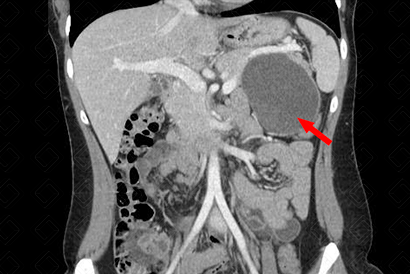

Descrição das figuras: Paciente do sexo feminino, 45 anos, realizou tomografia computadorizada do abdome com contraste venoso, fase portal evidenciando extensa lesão hipodensa, com realce parietal e periférico pelo meio de contraste, na cauda pancreática (setas vermelhas). O diagnóstico pela história clínica e características de imagem é sugestiva de cistoadenoma mucinoso. [cms-watermark]

• Tomografia computadorizada do abdome: O bservaremos lesão hipodensa, de densidade cística, com realce na parede do cisto, localizada, preferencialmente, no corpo/cauda pancreáticos (f iguras acima) .